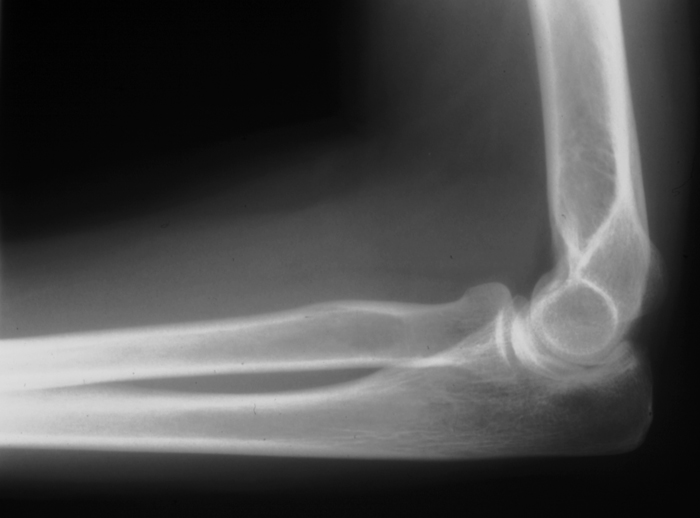

Radiology MS 28 - Normal Elbow

Identify: humerus, radius, ulna, capitulum, radial head, olecranon